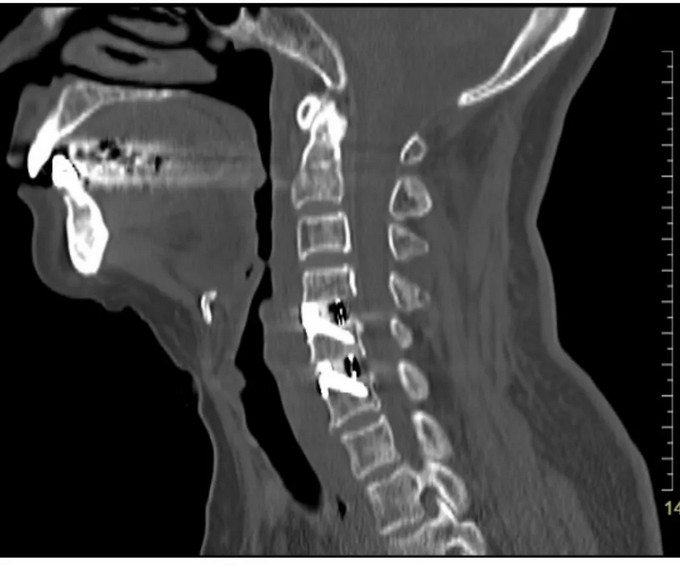

頸椎CT矢狀位

頸椎CT橫斷位 可以看到突出的骨贅已被切除

頸椎MRI矢狀位 頸神經(jīng)壓迫程度明顯減輕